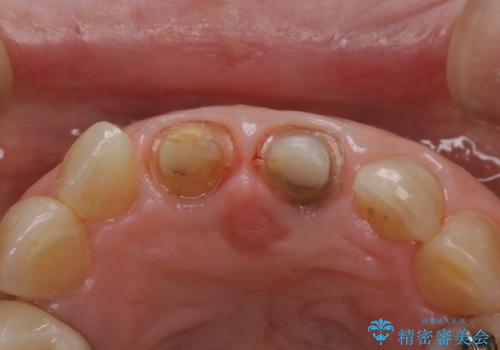

前歯の着色が気になる(失活歯)

- 前歯の着色が気になるということを主訴に来院された患者様です。

以前に、根管治療をされているみたいなのですが、そのまま放置されていてどんどん着色がひどくなり来院されました。

神経の治療をしている歯は、時間と共に色がどんどん変色していきます。

また、神経、血液供給がなくなってしまうので歯も脆くなっていってしまう為、歯が割れてしまうリスクもあります。